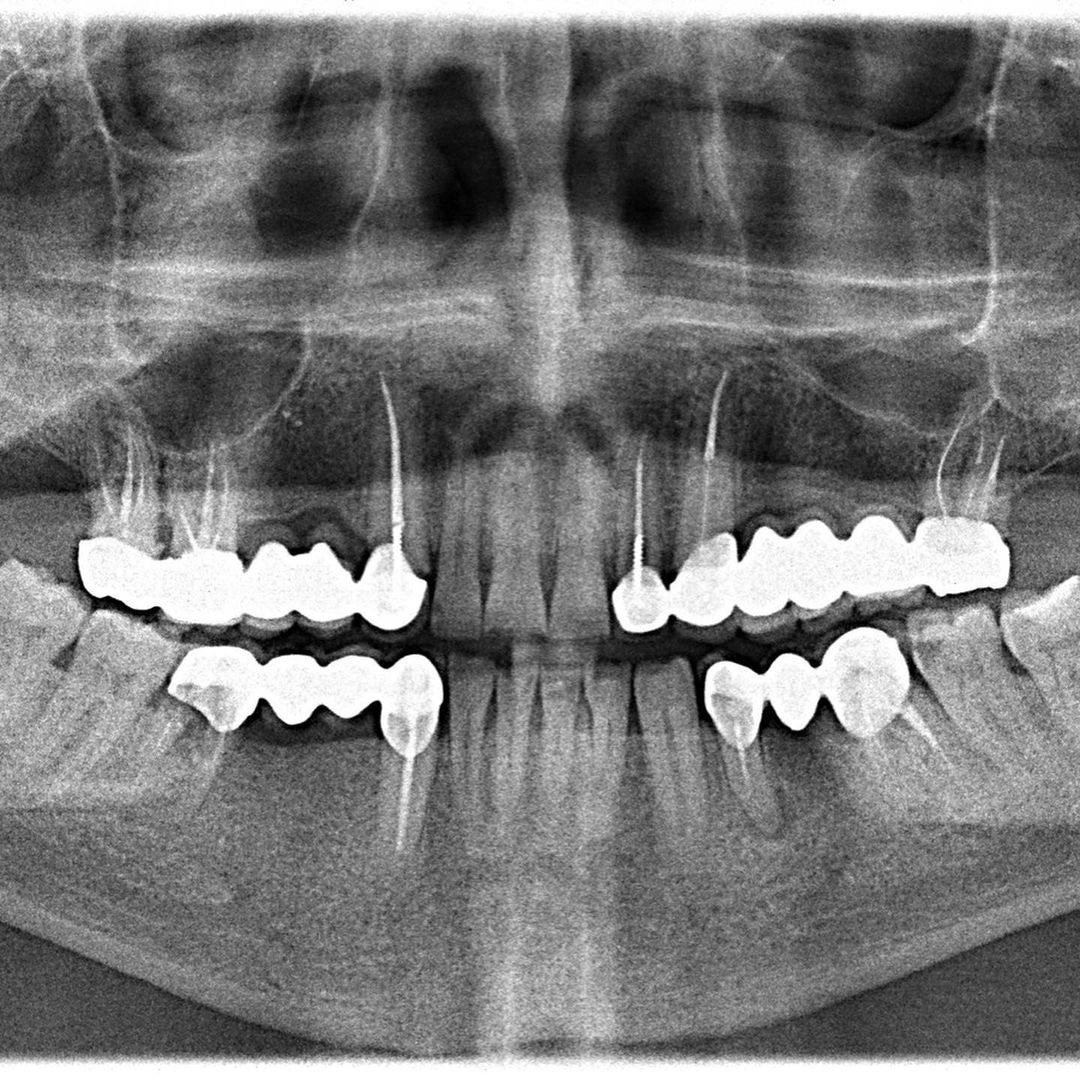

Медицинские Исследования: Кортикальная Пластинка на ОПТГ